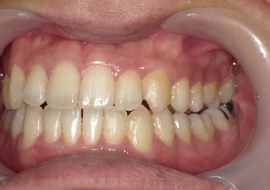

症例4

Before

After

| 主訴 | 上下前歯のがたつき |

|---|---|

| 年齢 | --- |

| 治療 期間 |

約9ヶ月 |

| 治療 内容 |

インビザラインiGoで上下顎の治療。 |

| 治療費 | ¥550,000(税込)/調整料含む |

| 治療のリスク | 矯正終了後は、リテーナーを指示通りに使用し、歯の後戻りを防ぐ必要があります。 |